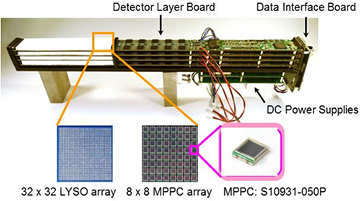

A four-layer DOI detector module comprising four detector layer boards including detectors, front-end and signal processing circuits, a data interface circuit board for transferring single-event data to a data acquisition server, and DC power supplies is shown in figure 1. The detector layer board has five detector units, each of which consists of a 32 × 32 LYSO scintillator array with a 1.2 mm pitch and 64 MPPCs (Hamamatsu S10931-050P: the active area is 3 mm × 3 mm, with 3600 pixels per 50 µm, Hamamatsu Photonics K.K., Japan) in an 8 × 8 arrangement. To fabricate a 32 × 32 scintillator array with a 1.2 mm pitch efficiently and precisely, we adopted an internally focused laser processing technique, termed sub-surface laser engraving (SSLE). SSLE produces micro-cracks that act as optical reflectors of scintillation photons inside a monolithic scintillator plate (Moriya et al 2010). A 2D 32 × 32 segmented array with a 1.2 mm pitch was fabricated to a monolithic LYSO scintillator plate with a 38.4 mm square cross-section. The scintillator thickness was designed to be 3 mm, 4 mm, 5 mm, and 8 mm toward the bottom layer, to ensure that the load for the count rate in every layer is equally sensitive for γ-rays, and the total scintillator thickness was 20 mm. The overall thickness for the four-layer DOI detector was 45.0 mm, including MPPCs, printed circuit boards, reflective and light shielding sheets, etc. The LYSO arrays were optically coupled to the MPPCs by a transparent silicon rubber compound (Momentive RTV615, Momentive Performance Materials, Inc., USA). The DOI detector modules were cooled using air cooling fans installed in a detector ring gantry head. Figure 2 shows a schematic drawing of a cross-section through the four-layer DOI detector.

Figure 1. Photograph of a four-layer DOI detector module.